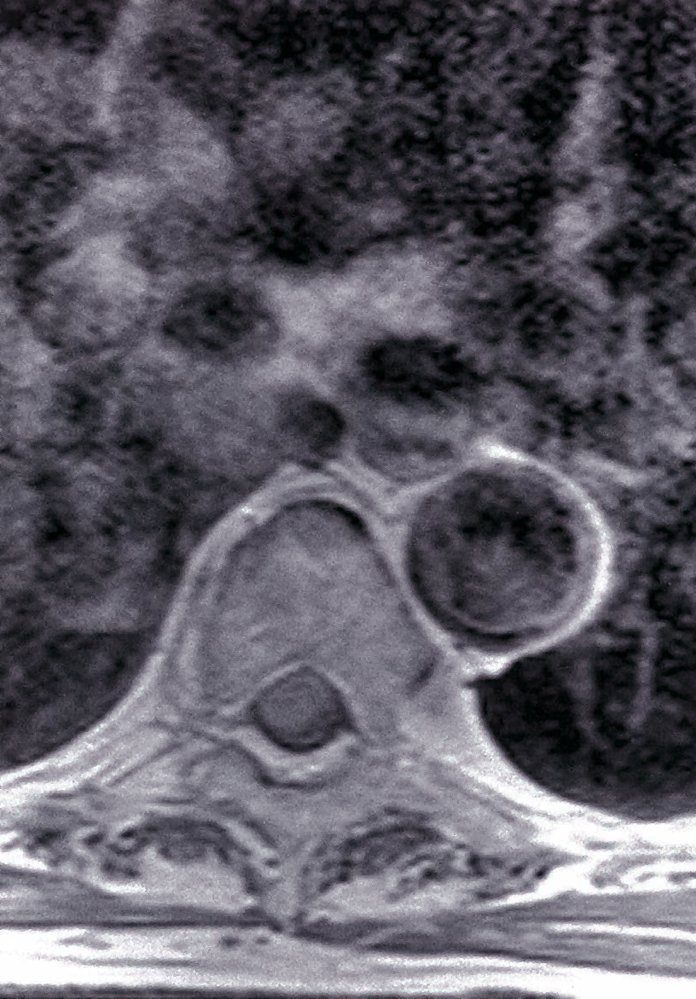

• Tumors (e.g., meningiomas, nerve sheath tumors, metastases, epidermoid cysts)

• MRI of the spine (imaging modality of choice) : determines the site of narrowing of the medulla and the underlying pathology

• Myelography (possibly with CT): if MRI is contraindicated (e.g., in patients with metal implants)